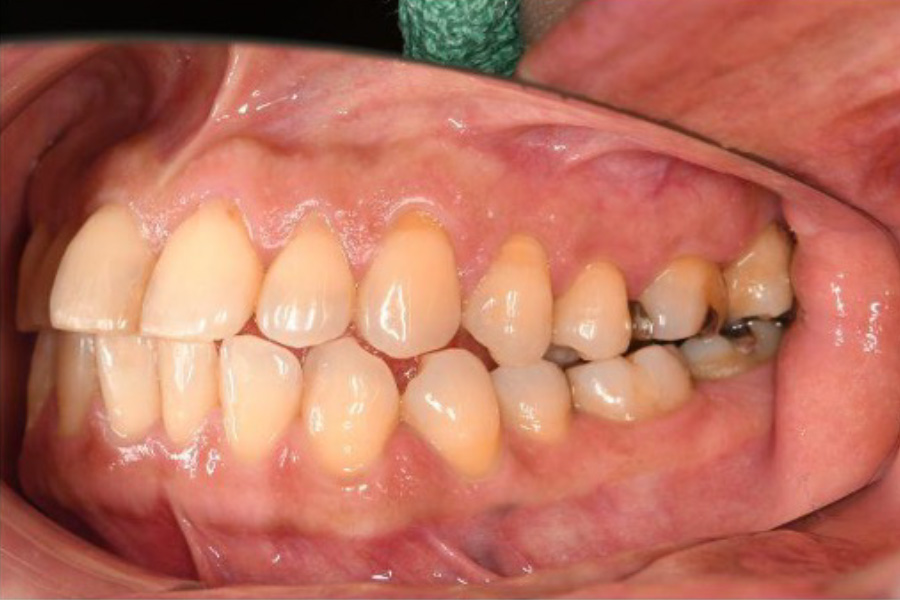

治療前